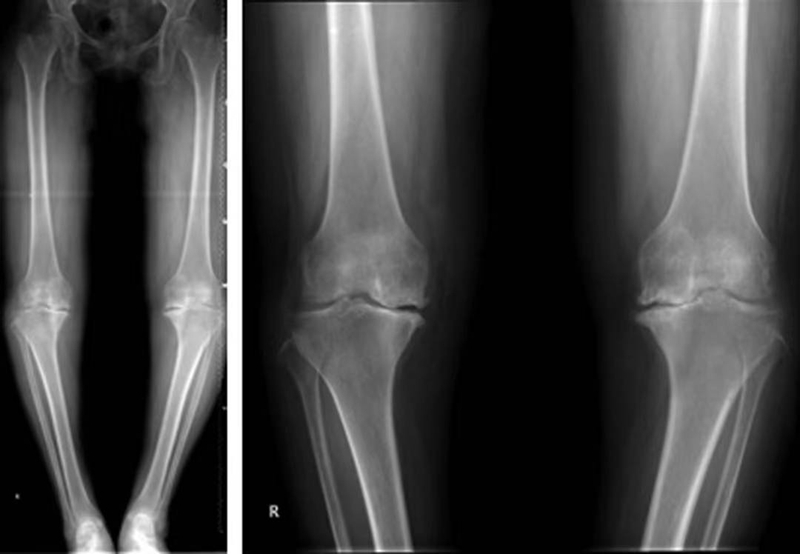

正常髌骨中心点应位于下肢轴线上或稍内侧(图1)。对于髌骨不稳定,膝关节正位像可见髌骨偏离正常的位置,向外侧移位(图2、图3)。

图3 膝关节正位X线成像显示了右膝髌骨偏离正常的解剖位置,明显向外侧移位